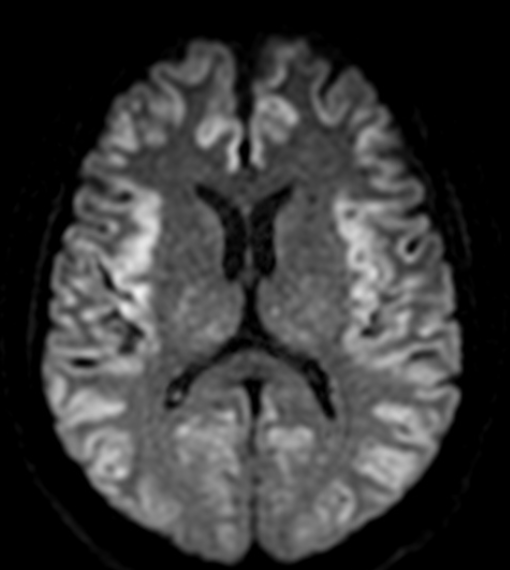

Imagem 1

Complicações neurológicas da Fludarabina